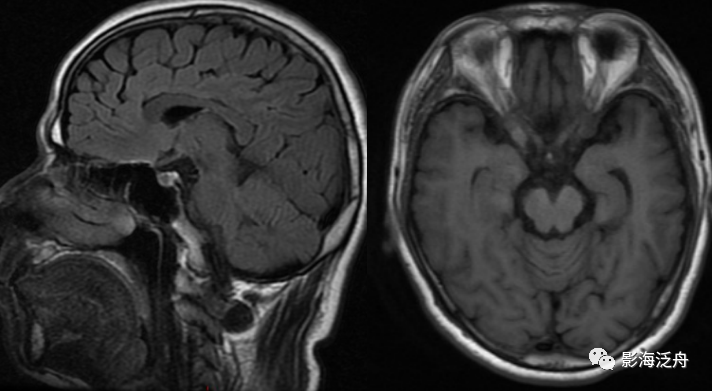

病例一:患者男,51岁,头晕1月余,神经系统查体无殊,血压正常。

病例一:烟雾病。如图所示,T2WI序列上在脑底池可以看到多发杂乱的细小流空血管影(红箭头),右侧侧裂池中大脑中动脉间断显示,且管腔粗细不均,而左侧大脑中动脉完全不显影(黄箭),两侧的大脑后动脉显示清晰(绿箭头)。脑底池中细小血管影增多的另一个常见原因多见于颅内感染,比如病毒性脑炎或隐球菌脑炎等。